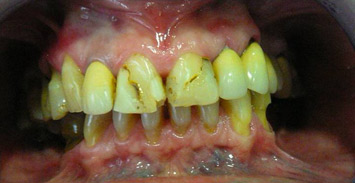

prije